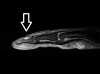

MRI : Glomus tumor

MRI로 진단할 수 있으나 초기여서 종양의 크기가 작을 경우에는 MRI로도 진단이 어렵습니다.